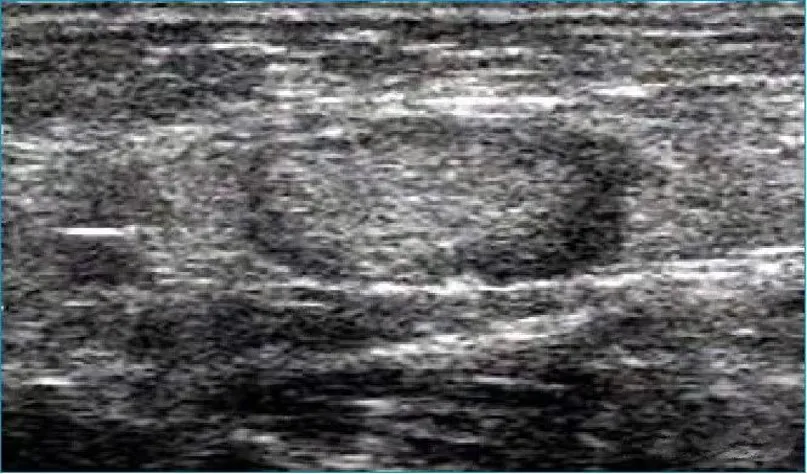

病例:右侧颈部肿痛3天,颈部可触及多个痛性结节。

超声描述:右侧颈部Ⅲ、Ⅳ区可见多发肿大的淋巴结,大者约21x6mm,呈椭圆形,皮质增厚,髓质居中,内部血流信号明显增多,呈放射状分布。